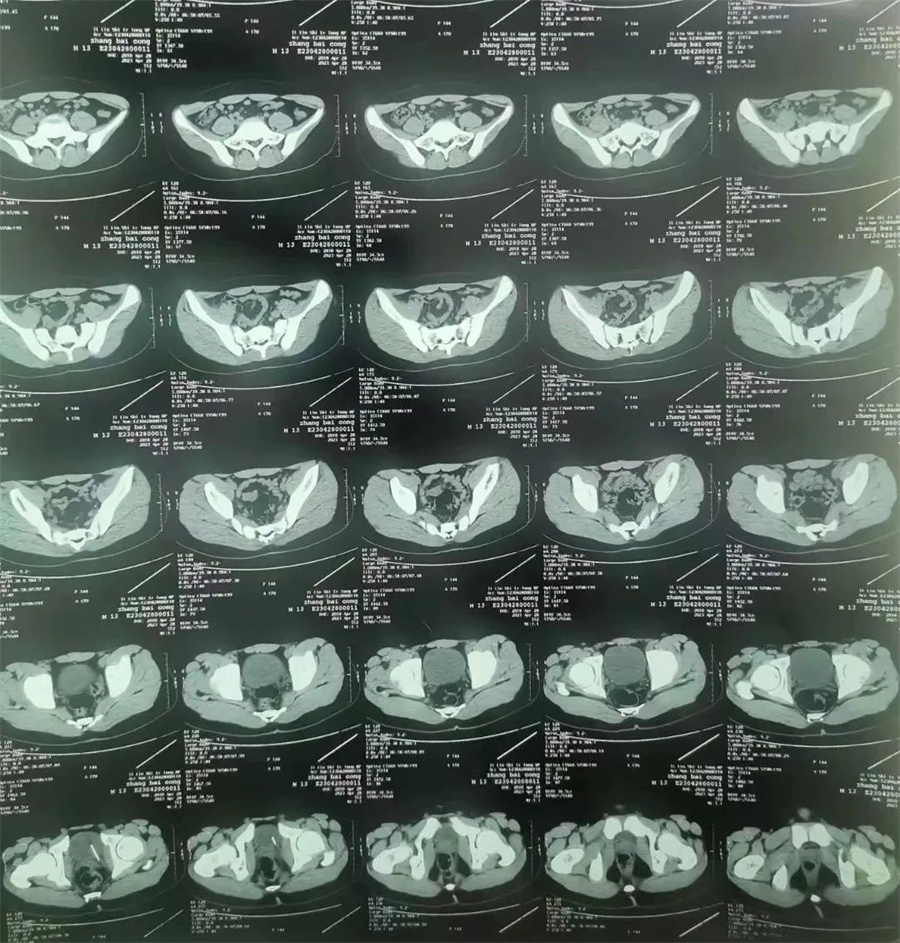

斌斌(化名),13岁,家住吉林市,因尿道疼痛、内裤有血,被家长带到当地医院就诊。医生经CT检查,发现斌斌膀胱侧壁扎着一根针,随时有穿破膀胱壁、损伤周围脏器可能。医生建议家长立即带斌斌到德州扑克游戏网 进行手术,将针取出。

。泌尿外科主任谢方达为其开辟绿色通道,以最快的速度进行救治。谢方达主任利用膀胱镜探查,很快确认了针在膀胱内的具体位置。

由于针已经在膀胱内存留一年多,表面布满铁锈和陈渣,加之男孩尿道细长弯曲。如果强行经尿道取针,发生副损伤或尿道内异物存留的风险极大。

如何简捷、确切、迅速地将针取出成了最大难题。最终,谢方达主任决定利用腹腔镜在患儿膀胱上打孔,进行微创取针。当长度约4厘米、表面锈迹斑斑的针呈现在众人面前时,家长紧张焦虑的心情终于缓解了。

术后,谢方达主任说,经过长时间的腐蚀,针变得非常脆,一夹就碎,不断掉渣,好在经过灌洗,残渣被冲洗干净了。